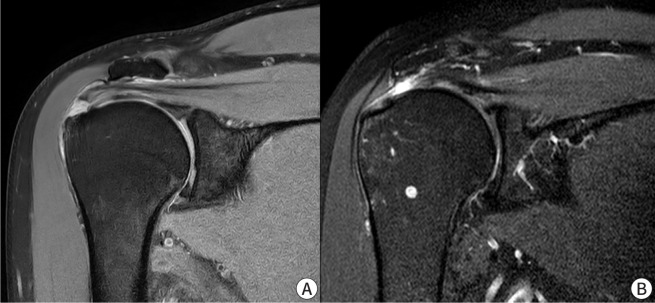

本综述的目的是为老年肩部疾病患者,特别是肩袖撕裂和骨关节炎的治疗提供一个全面的指南,并探索有效的非手术治疗方案。慢性肩袖撕裂通常是退行性的,而急性撕裂是由外伤引起的。这些撕裂的一个关键特征是肌腱变性伴有III型胶原蛋白优势,易使撕裂进展。肱骨关节的骨关节炎是由损伤软骨完整性的磨损变化引起的,导致疼痛和活动受限。准确的临床评估和成像,包括x线平片、超声和MRI,有助于诊断和指导治疗。体格检查强调活动度、肩袖强度和肩胛骨稳定性。治疗策略优先考虑缓解疼痛、保持功能和改善活动能力。非手术方式,包括运动、手工治疗和活动调整,是一线治疗方法,特别是对老年人。药理学方法包括非甾体抗炎药、皮质类固醇注射和神经性止痛药。类固醇注射有短期的好处,但反复治疗可能会损害组织的完整性。富血小板血浆是一种可促进肌腱愈合的再生选择,但结果不一,需要进一步研究。一个结构化的物理治疗方案,重点是活动范围和加强是必不可少的,与替代干预的明智使用。如果非手术方法不成功,应告知患者有关撕裂的潜在进展和未来可能需要手术干预的情况。包括关节活动和个性化运动方案在内的多模式方法,具有优化老年人功能结果和支持老年人独立的潜力。

The purpose of this review is to provide a comprehensive guide for managing older adult patients with shoulder diseases, specifically rotator cuff tears and osteoarthritis, and to explore effective nonsurgical treatment options. Chronic rotator cuff tears are typically degenerative, whereas acute tears result from trauma. A key feature of these tears is tendon degeneration accompanied by type III collagen predominance, predisposing tears to progression. Osteoarthritis in the glenohumeral joint arises from wear-and-tear changes that compromise cartilage integrity, leading to pain and restricted motion. Accurate clinical assessment and imaging, including plain radiographs, ultrasonography, and MRI, facilitate diagnosis and guide treatment. The physic-al examination emphasizes range of motion, rotator cuff strength, and scapular stability. Management strategies prioritize pain relief, function preservation, and improving mobility. Nonsurgical modalities, including exercise, manual therapy, and activity modification, constitute first-line treatments, especially for older adults. Pharmacological approaches involve NSAIDs, corticosteroid injections, and neuropathic pain medications. Steroid injections have short-term benefits, but repeated treatments may compromise tissue integrity. Platelet-rich plasma is a regenerative option that may improve tendon healing, but mixed findings highlight the need for further investigation. A structured physical therapy program focusing on range of motion and strengthening is essential, with alternative interventions used judiciously. Patients should be counseled regarding the potential progression of tears and the possible need for future surgical intervention if nonsurgical methods are unsuccessful. Multimodal approaches, including joint mobilization and personalized exercise regimens, hold potential for optimizing functional outcomes and supporting independence in older adults.